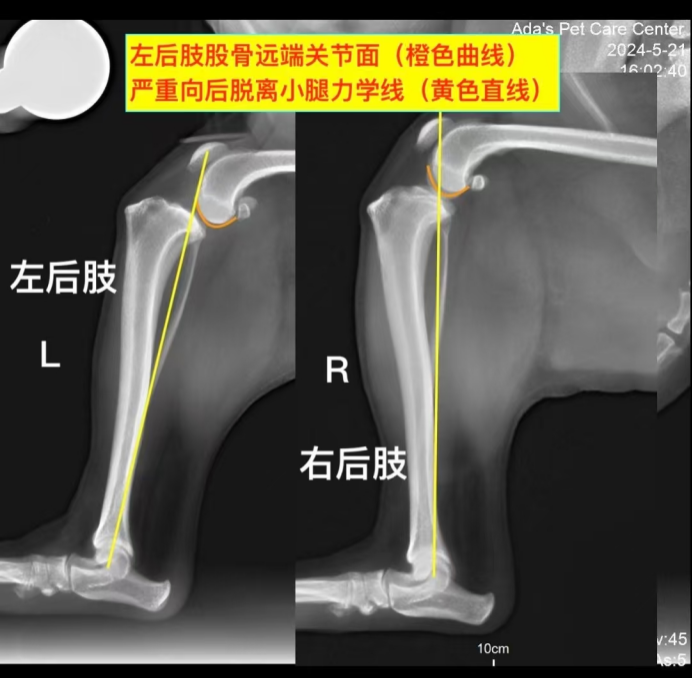

SymptomsThis 7-month-old Golden Retriever had been showing signs of vomiting and a decreased appetite for a while. Lately, the dog’s condition worsened with a sudden drop in energy, making its owner very concerned. The dog became more lethargic and weak,